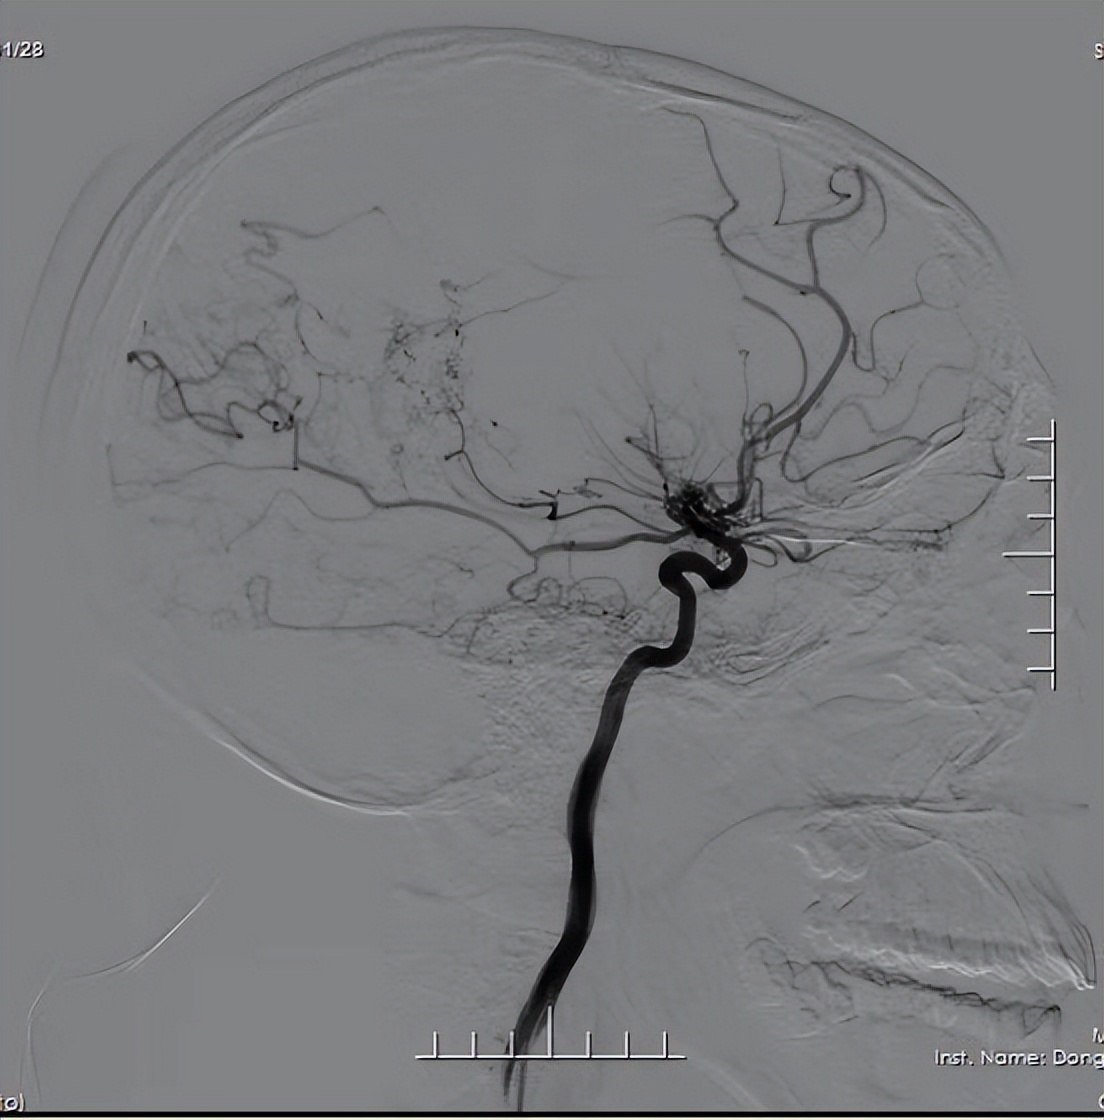

只因在做脑血管造影时

会呈现许多密集成堆的小血管

形似烟雾而得名